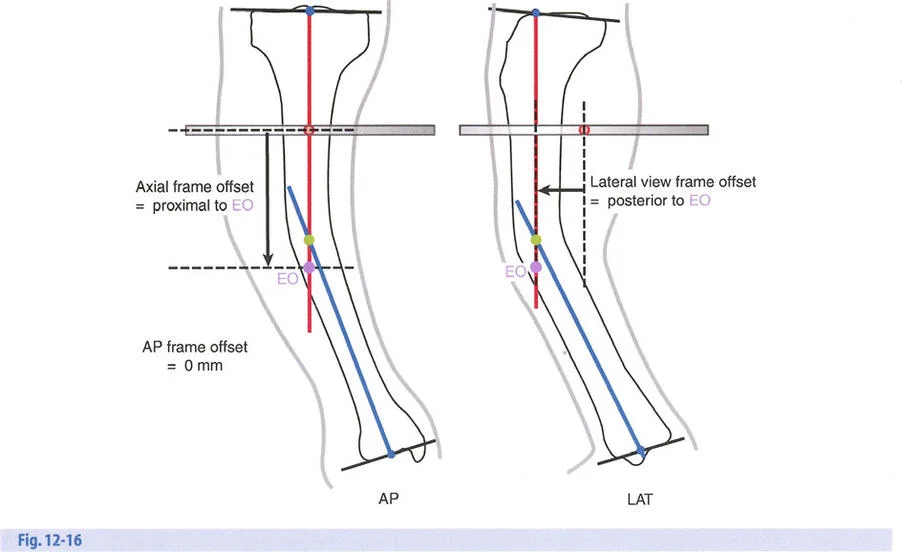

هذا الدليل الشامل يستعرض الاعتبارات الحاسمة لتطبيق الأجهزة، وتحديد مواضع المفاصل الاصطناعية (المفصلات)، وآليات الشد، والتسلسل الاستراتيجي للتصحيحات التدريجية. سواء كان الجراح يستخدم مثبتات إليزاروف الدائرية التقليدية، أو أنظمة الهيكسابود الحديثة (مثل جهاز تايلور الفراغي Taylor Spatial Frame)، أو المثبتات أحادية الجانب، فإن القواعد الهندسية التي تحكم مركز دوران الانحراف (CORA)، ومحور تصحيح الانحراف (ACA)، وانحراف المحور الميكانيكي (MAD) تظل مطلقة ولا تقبل الخطأ.

- أنظمة الهيكسابود الحديثة (مثل جهاز تايلور الفراغي Taylor Spatial Frame): تستخدم ست دعامات متداخلة (struts) متصلة بحلقتين. يتم التحكم فيها بواسطة برنامج حاسوبي يقوم بحساب التعديلات اليومية بدقة فائقة لتصحيح التشوه في ستة اتجاهات.

إتقان معدلات الشد: قاعدة المثلثات المتشابهة

القاعدة الذهبية البيولوجية لتوليد العظم بالشد، التي وضعها إليزاروف بعد عقود من التجارب على الحيوانات والبشر، هي معدل شد يبلغ 1 ملم يوميًا. يتم تقسيم هذا عادة إلى زيادات قدرها 0.25 ملم كل 6 ساعات لمحاكاة النمو المستمر للوحة النمو.

ومع ذلك، فإن الخطأ الشائع، الذي قد يكون كارثيًا أحيانًا للجراحين المبتدئين، هو سوء فهم أين يجب أن يحدث هذا الـ 1 ملم يوميًا.

معدل 1 ملم/يوم ينطبق بشكل صارم على القشرة المقعرة للعظم في موقع قطع العظم (الحافة الأمامية للإسفين المفتوح). نظرًا لأن الجهاز (قضيب الشد أو دعامة TSF) يقع على مسافة من العظم، خارج غلاف الأنسجة الرخوة، فإنه يتحرك على طول قوس أكبر بكثير. إذا وجهت المريض لشد القضيب بمعدل 1 ملم يوميًا، فإن العظم الفعلي سيُشد بجزء ضئيل من هذا المعدل، مما يؤدي إلى التصلب المبكر لموقع قطع العظم.

حساب معدل الشد الحقيقي

لحساب المعدل الصحيح للشد عند المفصلة، نستخدم قاعدة المثلثات المتشابهة، والتي تعتمد أساسًا على القاعدة الهندسية للدوائر متحدة